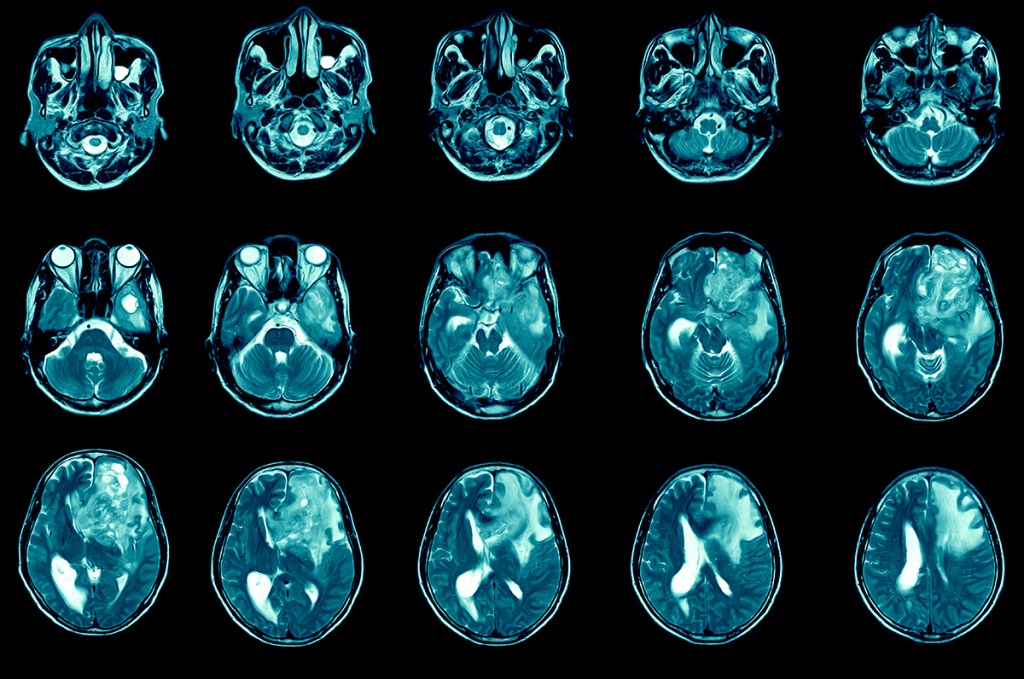

One of Maus’ primary targets is the solid tumor problem, which is created in part by cell diversity, denser mass, and threats to the survival of CAR-T cells in the hostile immune environment around the malignancy. Last year, she teamed up with Harvard neurosurgeon Bryan Choi to test the therapy against glioblastoma, a devastating brain tumor that kills more than 90 percent of patients within five years. They tackled the diversity issue by engineering a two-pronged CAR that targeted two molecules typically found on the surface of different cancer cells, broadening the T-cells’ attack. The first three participants in the study saw dramatic improvements in their cancer, though the effects were durable in only one. Follow-up data on a total of 10 patients was presented at the American Society of Clinical Oncology this month.